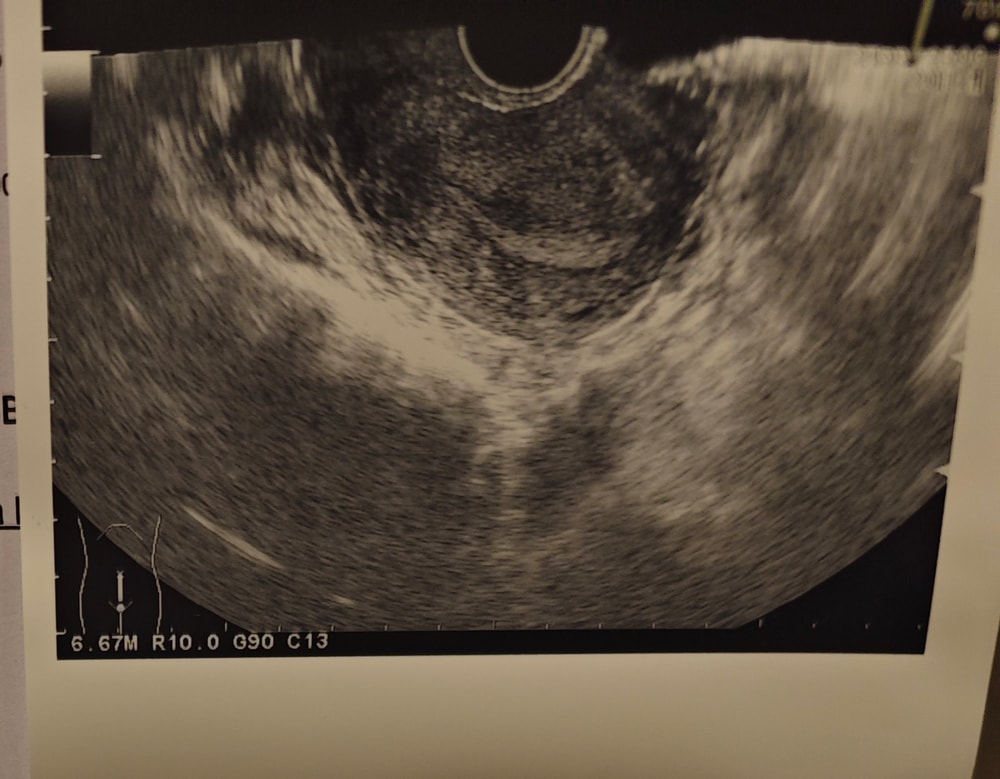

Кити, Изображениепосмотрите , пожалуйста, уже, боюсь, что цикл ануволотерный

вам в узи написали - окулировавший фолликул, наверное врач просто некорректно выразилась про ЖТ

Арина, спасибо, я просто рассчитывала увидеть именно размеры ЖТ... Вроде как по ЖТ определяется какая была овуляция